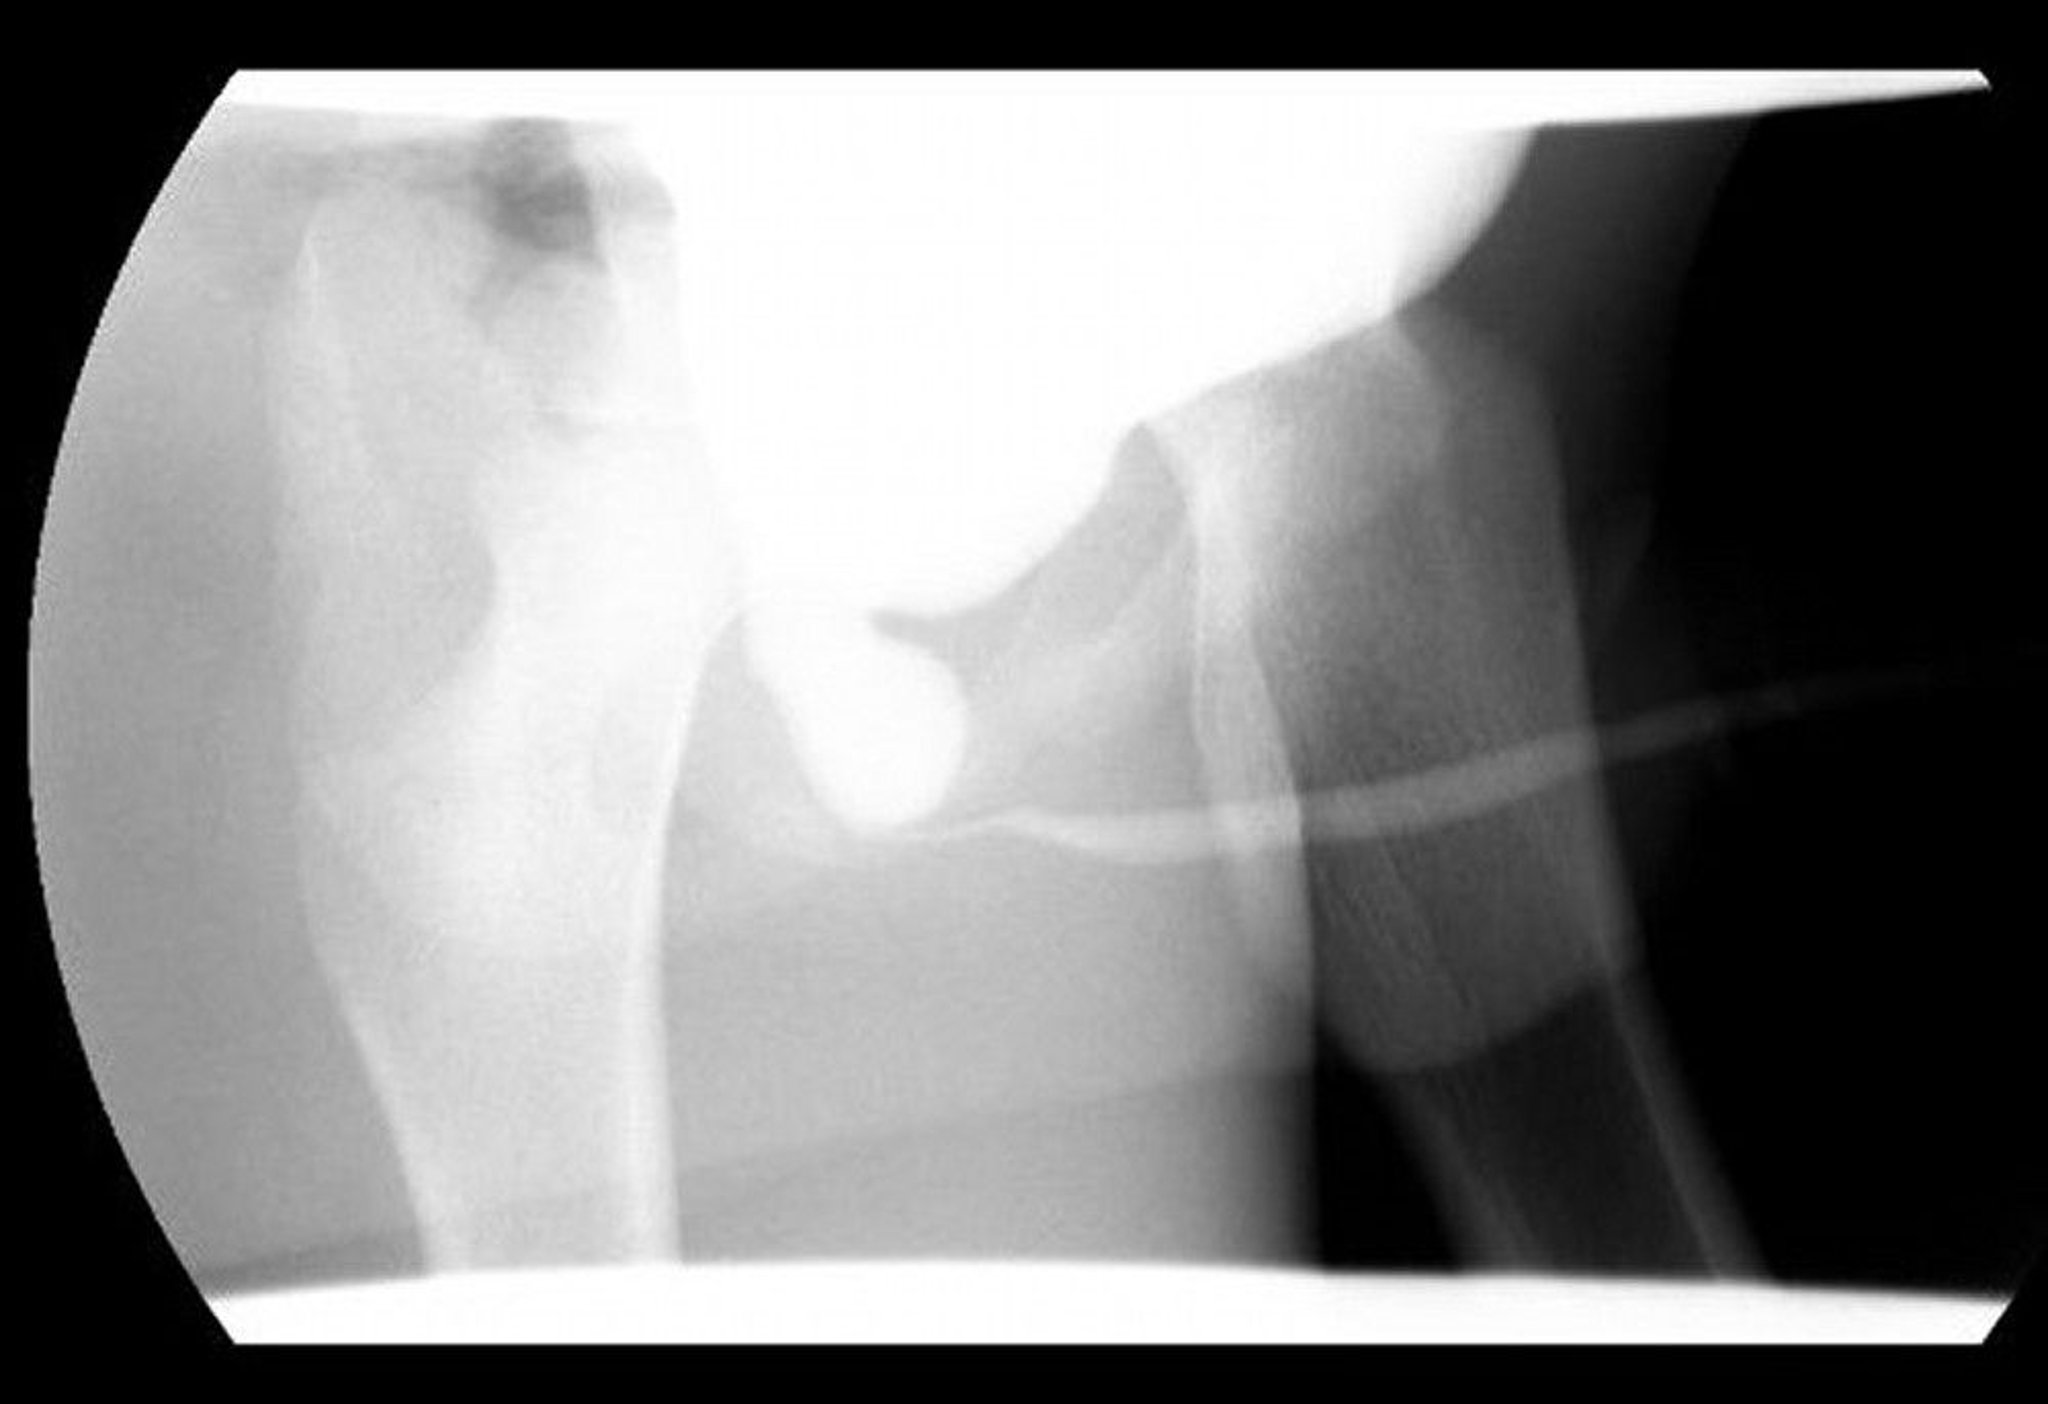

Dieses Bild der Miktionszystourethrographie (VCUG) zeigt eine dilatierte hintere Harnröhre mit distaler Obstruktion aufgrund von hinteren Urethralklappen.

Image courtesy of Drs. Ronald Rabinowitz und Jimena Cubillos.